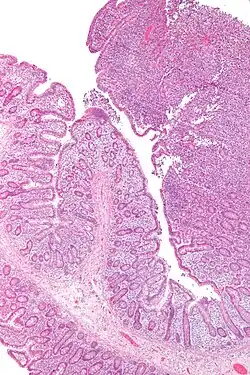

Micrograph of an enteropathy-associated T cell lymphoma (upper right of image), a type of T cell lymphoma. H&E stain.